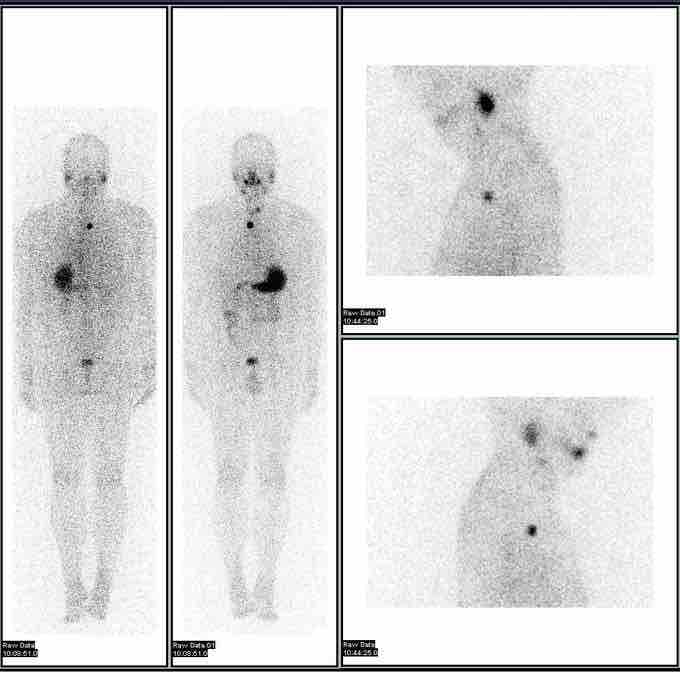

Iodine-123 whole-body scan

These images are scans used in the evaluation of thyroid cancer using the isotope iodine-123.

Common isotopes that are used in nuclear imaging include: fluorine-18, gallium-67, krypton-81m, rubidium-82, nitrogen-13, technetium-99m, indium-111, iodine-123, xenon-133, and thallium-201.